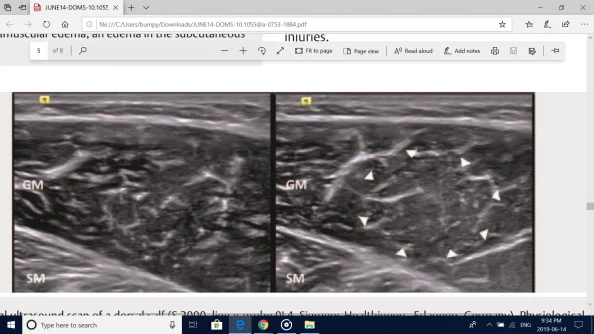

▶ Fig.4 Transversal ultrasound scan of a dorsal calf (S 2000, linear probe 9L4, Siemens Healthineers, Erlangen, Germany). Physiological conditions (A), and DOMS conditions within direct signs of ultrastructural muscle damage, 48 hours after exhausting exercises (B) .Triangles: demonstrating a diffuse hyperechoic area, located at the center of pain; GM: gastrocnemius medialis muscle, SM: Soleus muscle.